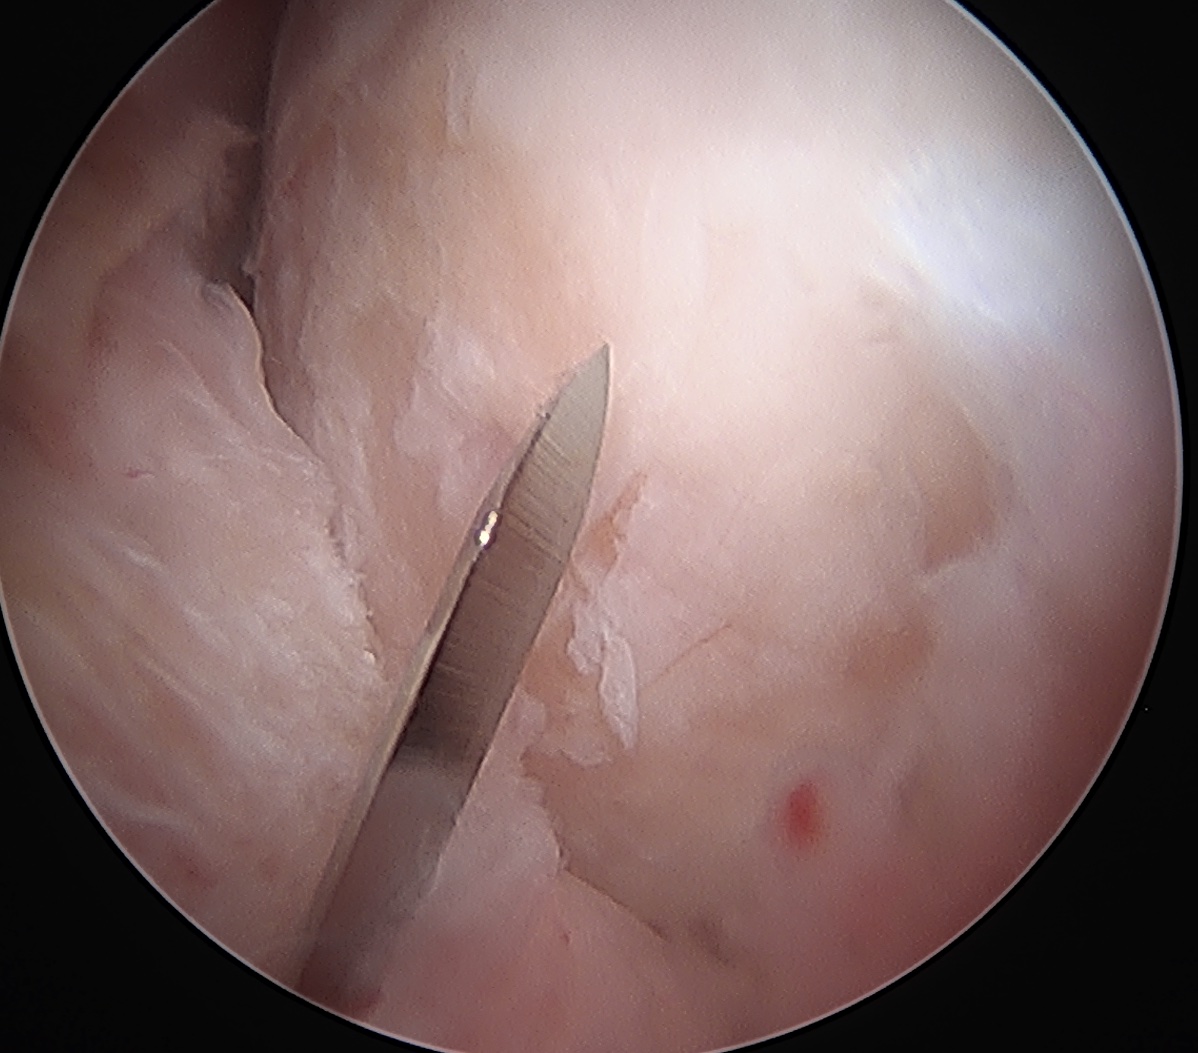

Interportal capsulotomy through PALA Interportal capsulotomy through midanterior

Interportal capsulotomy

Critical to allow instrumentation

- divide capsule between PALA and midanterior portals

- use combination of knife / diathermy

- preserve capsule for later repair